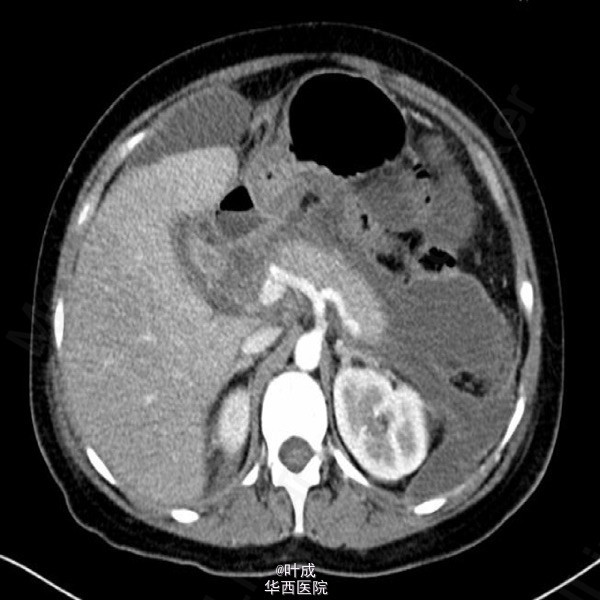

患者女,39岁,因“腹痛2天”入院。患者既往否认胆道疾病病史。入院查体:T:36.5oC,P:130次/分,R:28次/分,BP:135/85mmHg,BMI=25kg/m2。心肺查体无特殊。腹部饱满,全腹肌紧张,上腹压痛,无反跳痛,腹部未触及包块。肝脾肋下未触及。辅助检查:血清淀粉酶 827 IU/L,脂肪酶 720IU/L;血常规:血红蛋白 193g/L,白细胞 8.02*10^9/L,中性粒 80.2%;血甘油三酯 20.33mmol/L,胆固醇 10.80mmol/L;血钙 1.54mmol/L;胸腹部平扫CT示:胰腺肿胀,实质密度不均匀减低,周围脂肪间隙模糊,散在渗出积液影,腹、盆腔、双侧胸腔积液,肺部感染(图2);腹部超声提示脂肪肝,肝内外胆管未见扩张。入院APACHE II评分13分。入院诊断:急性胰腺炎(重度 高脂血症型),肺部感染)。入院后予禁食,控制补液,奥曲肽抑制胰腺分泌,埃索美拉唑抑酸,导泻,加贝酯抑制胰酶,哌拉西林舒巴坦抗感染,维持电解质平衡,补充丙氨酰谷氨酰胺等治疗。患者腹痛症状逐渐缓解,每日出入量大体平衡,但腹胀、气紧症状逐渐加重,沟通后予无创呼吸机辅助通气(中途尝试停用未遂,共使用13天),期间血气分析血氧分压变化见图1(期间存在误采静脉血可能)。患者气紧较前缓解,仍有腹胀,纳差,肛门排期排便可,复查腹部增强CT:胰腺未见明显坏死灶,与之前比较,腹腔积液增多,部分包裹,炎症累及区域脂肪密度降低。双侧胸腔少量积液并双下肺局部肺不张(图3-4);复查甘油三酯 3.63 mmol/L,血清白蛋白>40g/L。治疗上逐步加强肠内营养,予螺内酯利尿,患者腹胀较前有所缓解。